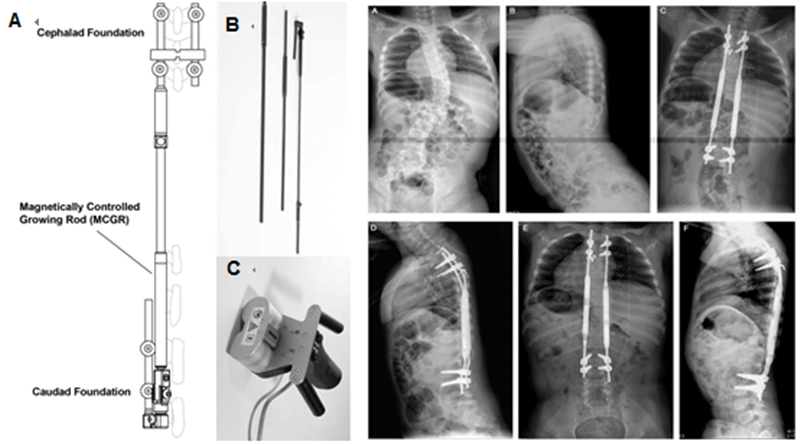

1.3.2 磁力控制生长棒

2012年,Akbarnia等[8]报道了MCGR的动物实验及初步临床结果(图 5),实验动物研究中,磁力控制生长棒(magnetically controlled growing rod, MCGR)最终延长达预期80%,且未发现相关并发症。2013年Akbarnia[9]再次报道了14例临床初步结果(图 2 右),平均随访10个月(5.8-18.2),未观察到相关严重并发症,其结果初步验证了其安全性。MCGR相关研究随之成为热点。

图5 左图A:Akbarnia[8]于2012年首次报道MCGR,整个装置包括:带有可延长撑开器的生长棒(B),体外控制伸缩的螺旋磁芯(C)。右图为Akbarnia[9]于2013年报道中的1例5.5岁神经肌肉性EOS患儿。术前正侧位X片(A,B)示右胸弯45°;双棒MCGR术后正侧位X片(C,D);E和F为患儿术后7个月的定期延长后正侧位X片,示T1–T12和T1–S1分别达到12mm和31mm